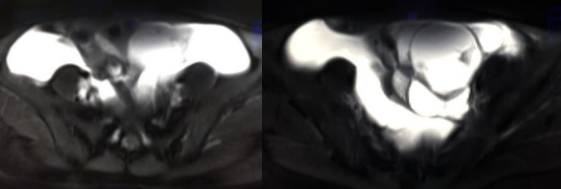

MR检查:

病理结果:黄体血肿

根据时间不同MR信号也有所不同,TIWI脂肪抑制序列可以鉴别脂肪和出血。

卵巢囊肿:呈均匀的T1WI 低信号,T2WI 高信号,边界清楚,壁薄,大多数病灶直径≤5 cm,但囊肿的起源及定性诊断困难。

巧克力囊肿:常呈多发的单囊或多囊改变,病灶大小不等,囊壁厚薄不均,囊内信号复杂,囊内或各囊腔间血液因出血时期不同,信号常呈多样性,囊肿内反复出血、破裂,形成相互粘连的多房性囊肿,是其较为特征性的表现。

在鉴别卵巢畸胎瘤、出血性囊肿或巧克力囊肿时,MR 脂肪抑制T1WI 可明确肿块内高信号成分是脂肪还是出血,同时由于脂肪组织与非脂肪组织的共振频率不同,在两者交界处沿磁场频率编码方向出现化学位移伪影,但出血性囊肿与巧克力囊肿的鉴别有时较为困难。